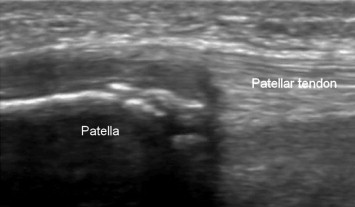

US findings are the same as those in OSD: cartilage swelling, patellar tendon swelling at its proximal insertion and patellar fragmentation at its distal pole [6] (Fig. 3). X-ray examination may show patellar fragmentation and, in late stages of the disease, calcification of the patellar tendon.

Fig. 3.

Sinding-Larsen–Johansson syndrome. Sagittal US scan: the patellar fragmentation is clearly visible at its distal pole with patellar tendon thickening at the proximal insertion and cartilage swelling.